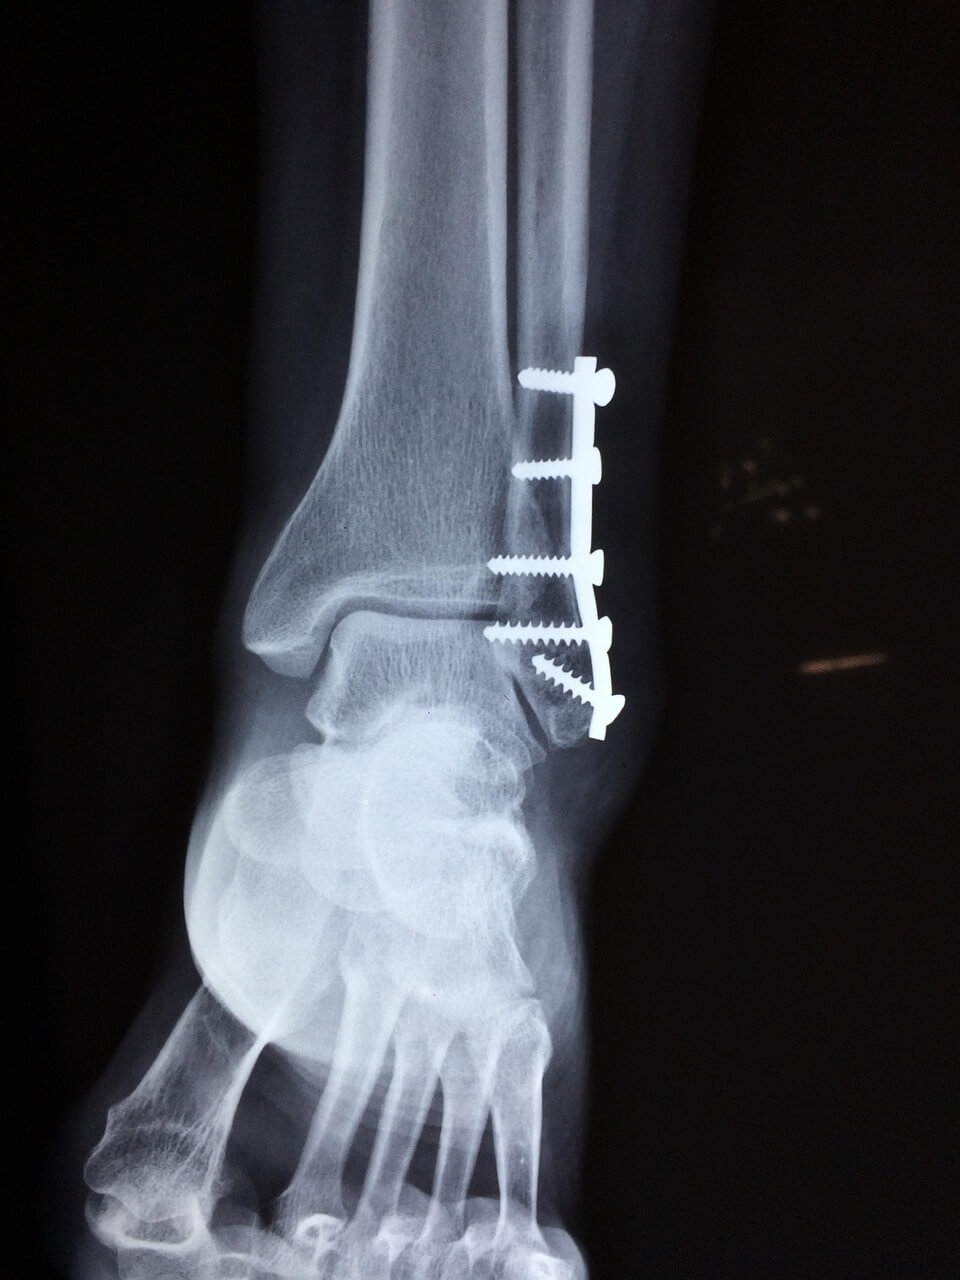

- 가벼운 충격에도 손목·발목 통증이 오래 감

- 검사 개요

- 이중에너지 X선 흡수계측(DEXA): 골밀도 표준

- 혈액검사: 비타민D(25(OH)D), 칼슘, 마그네슘

- 필요 시 척추 단순 촬영(압박골절 확인)